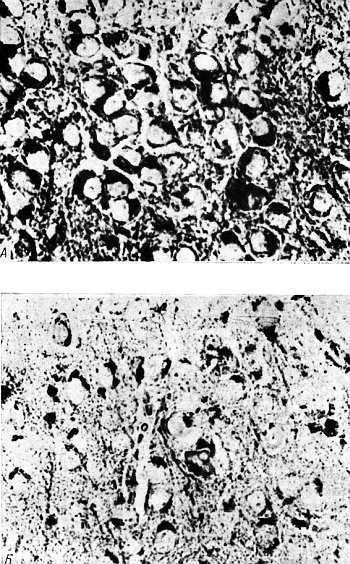

Рис. 6.2. Окрашивание липофусцина нильским голубым в нейронах коры головного мозга мышей в возрасте 6 мес; ×600 [33, 34].

А. Контроль. Б. После введения центрофеноксина в течение 5 мес